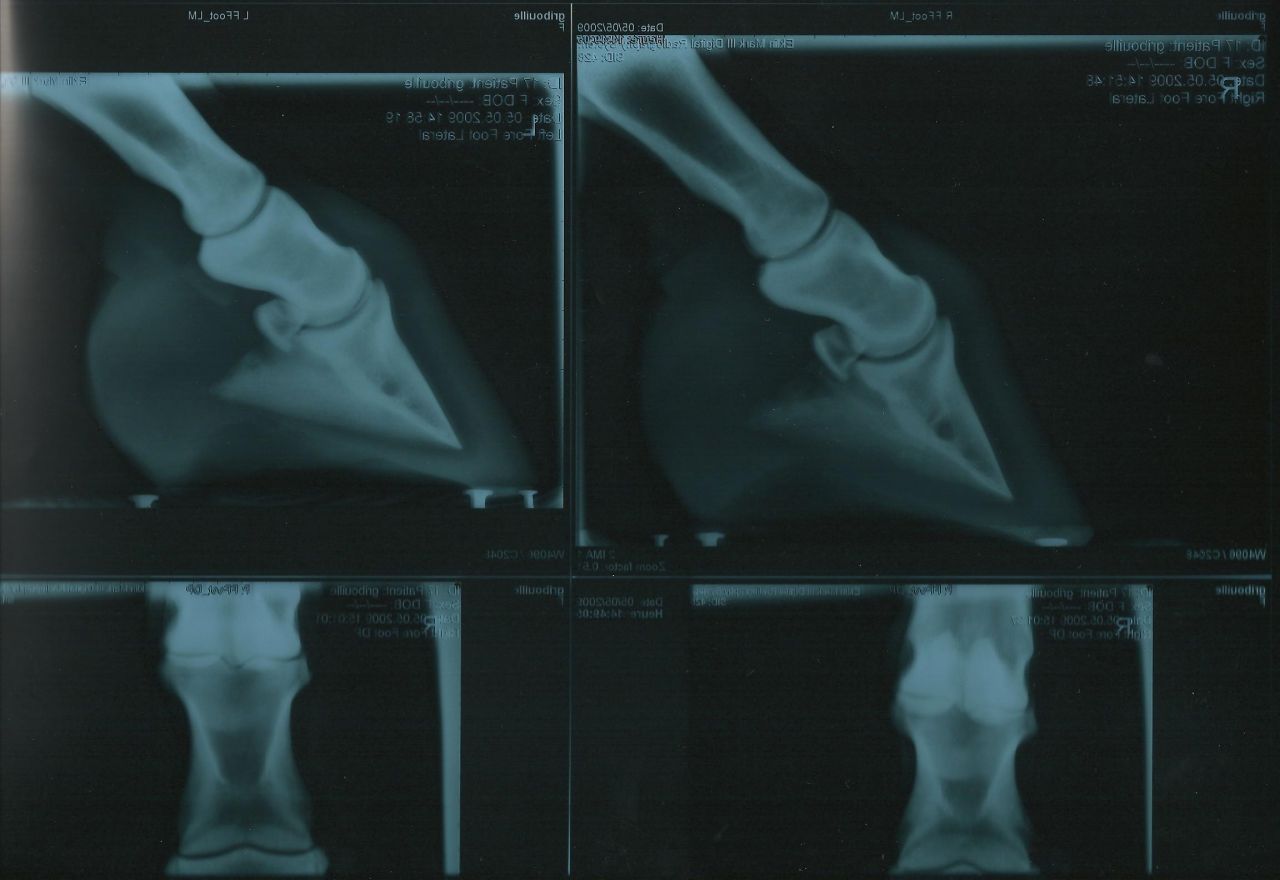

Par griblorh : le 17/08/10 à 19:19:26

Déconnecté | quelqu'un peut réduire ces radios? |

Par tata : le 17/08/10 à 19:29:05

| Dire merci | Et c'est pécisément là qu'on voit les effets de la génétique: zavez vu la différence de longueur d'os de la 3eme phalange? Comment peut on imaginer parer ces deux chevaux de la meme manière. Particulierement concernant la longueur du pied. ![]() |